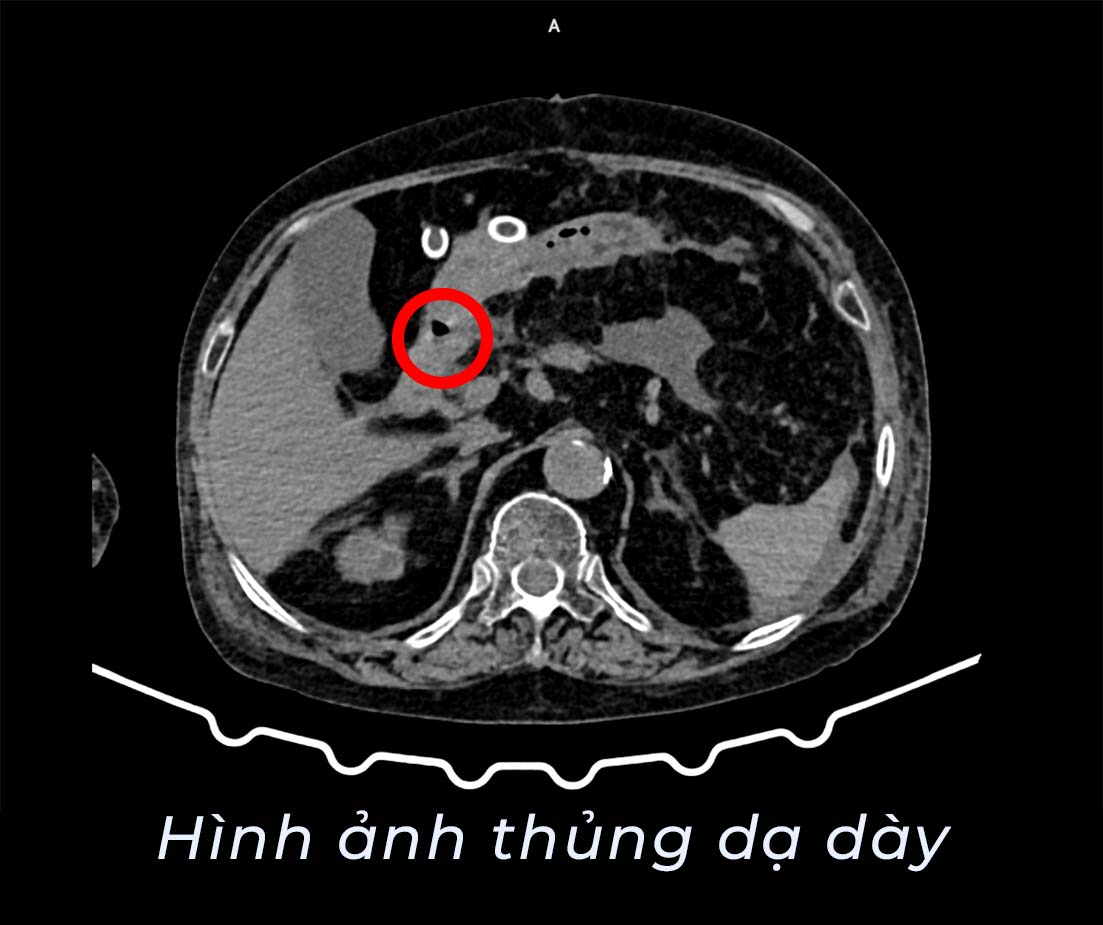

Nhận định đây có thể là tình trạng bệnh lý nguy hiểm trong ổ bụng, các bác sĩ đã nhanh chóng chỉ định chụp cắt lớp vi tính ổ bụng. Kết quả cho thấy hình ảnh khí tự do trong ổ bụng, kèm dịch ổ bụng, thâm nhiễm quanh dạ dày, đây là dấu hiệu điển hình gợi ý thủng tạng rỗng. Ngoài ra, các bác sĩ còn phát hiện bệnh nhân có nang gan trái, nang thận hai bên và sỏi thận hai bên.

Sau khi hội chẩn chuyên môn, các bác sĩ xác định bệnh nhân bị thủng dạ dày – một tình trạng cấp cứu ngoại khoa nguy hiểm, nếu không được xử trí kịp thời có thể dẫn tới viêm phúc mạc, nhiễm trùng nặng, đe dọa tính mạng, đặc biệt ở người cao tuổi.